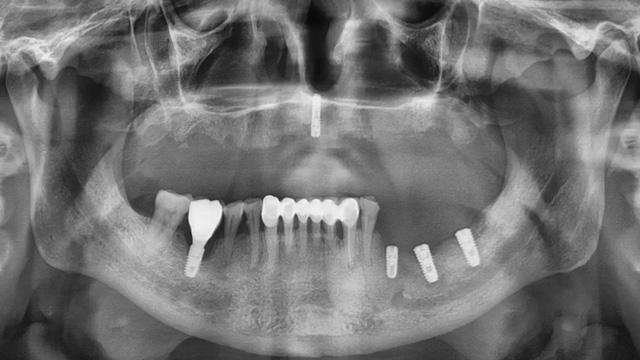

经CBCT检查所见,沈老师的口腔情况比较复杂:下面原有的四颗种植牙只有一颗有牙冠,其余三颗种植体情况尚可,可以安装牙冠,上半口牙列缺失,牙槽骨里还埋着一个种植体。“这颗植体的位置没有骨板,不能受力,没有安装牙冠的条件。好在它位置在正中,不影响种植手术和牙冠修复。”

治疗前口腔全景片